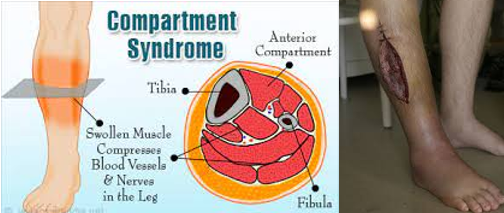

Assessment of Musculoskeletal Injuries

Assess for the 5 Ps to rule out complications of compartment syndrome:

Pain (increased and out of proportion)

Pulselessness

Pallor

Paresthesia

Paralysis

Also assess the 5 Ps before and after immobilization, as well as any time the patient reports a change in sensation.

Complications for Splints or Casts

Compartment Syndrome:

Occurs when there is increased pressure in an enclosed space, such as a cast.

This results in decreased blood flow.

The patient will typically report sudden increased pain (this is due to tissue dying).

Ischemia occurs, followed by necrosis of tissue.

An emergency fasciotomy must be performed to save the tissue and extremity.

These patients will require a skin graft sometime in the future.